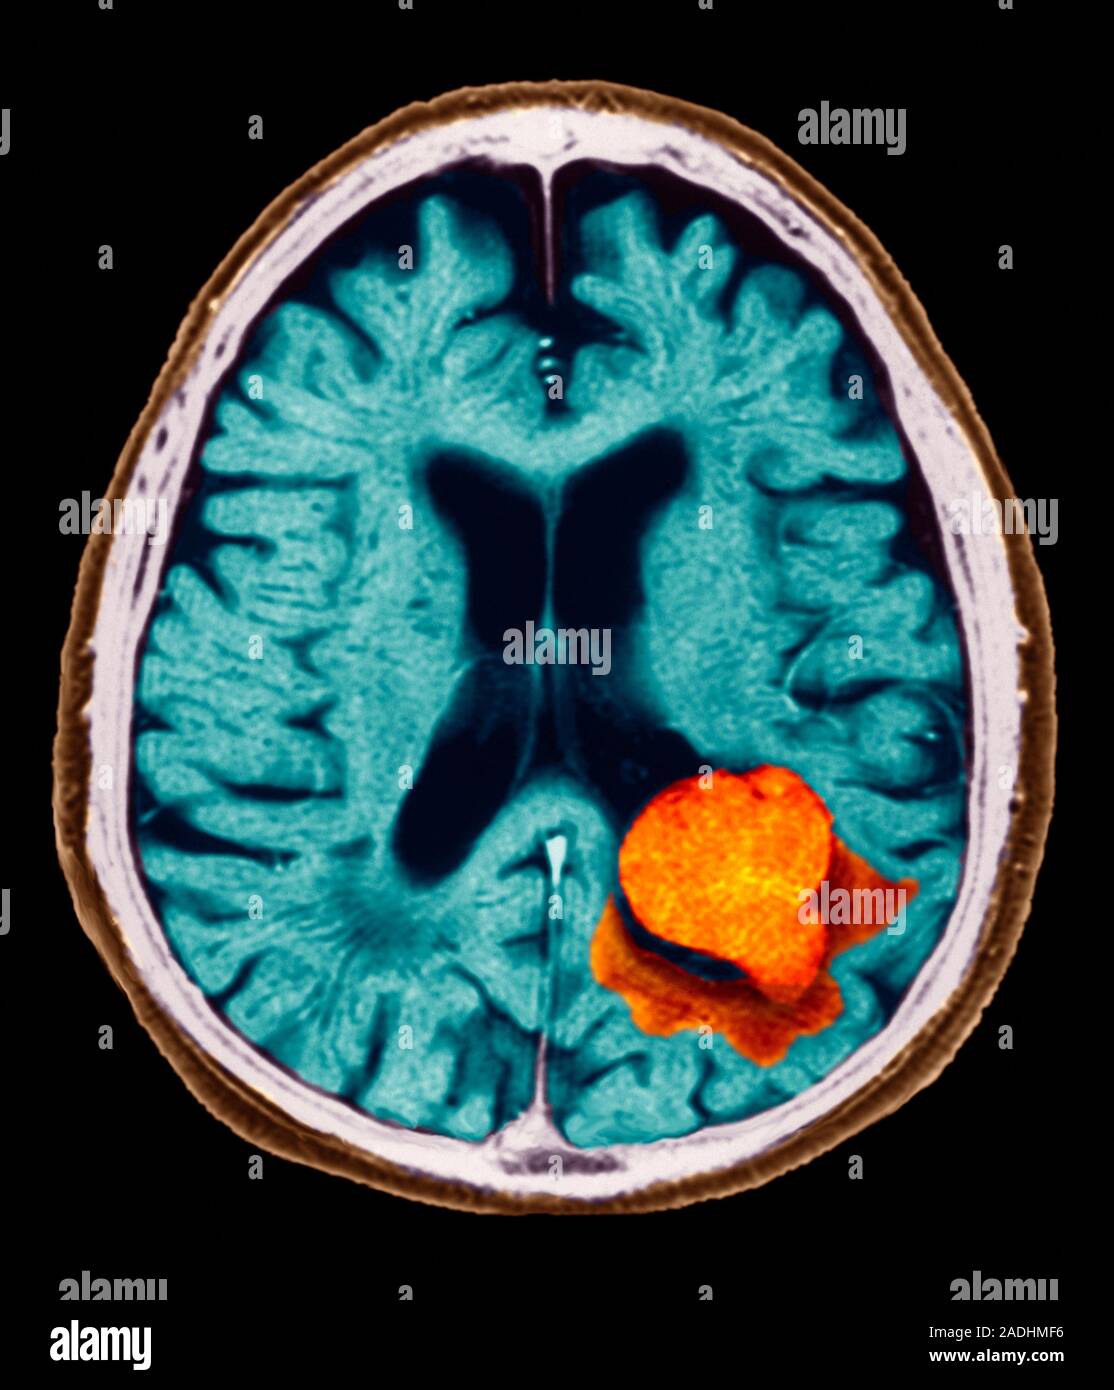

From www.alamy.com

Brain lesion. Coloured axial (horizontal) resonance imaging Motion Blindness Brain Lesion although the higher brain mechanisms of seeing moving objects have been deeply investigated, motion blindness remains a rare and enigmatic symptom. 95 rows cerebral akinctopsia is a syndrome in which a patient loses specifically the ability to perceive visual. what is akinetopsia? It’s due to a problem with the brain rather than the eyes, which is why. Motion Blindness Brain Lesion.